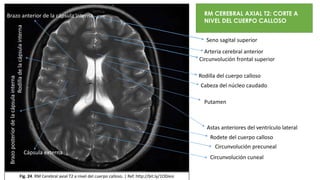

Rodilla del cuerpo calloso

Putamen

Cabeza del núcleo caudado

Astas anteriores del ventrículo lateral

Rodete del cuerpo calloso

Brazo anterior de la cápsula interna

Rodilladelacápsulainterna

Brazoposteriordelacápsulainterna RM CEREBRAL AXIAL T2: CORTE A

NIVEL DEL CUERPO CALLOSO

Seno sagital superior

Circunvolución frontal superior

Arteria cerebral anterior

Cápsula externa

Circunvolución precuneal

Circunvolución cuneal

Fig. 24. RM Cerebral axial T2 a nivel del cuerpo calloso. | Ref. http://bit.ly/1O0Jesi